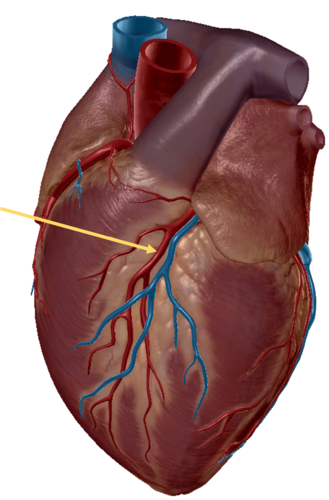

anterior inter ventricular sulcus

right coronary artery

circumflex artery

great cardiac vein

anterior inter ventricular artery

left pulmonary veins

left pulmonary artery